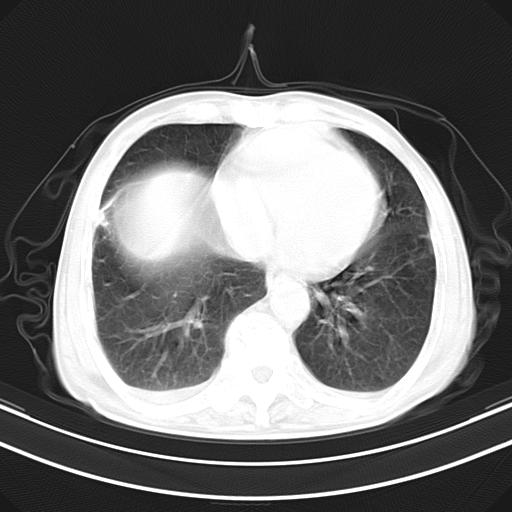

影像所见:右上肺见一巨大厚壁空洞,内壁欠光整,右上肺广泛斑片状、大片状模糊阴影。

诊断意见:考虑右上肺巨大含气囊肿并感染,建议继续治疗后复查。

不支持点:空腔壁较厚,欠光滑。询问病人是否有反复感染病史?

影像所见:右上肺见一巨大厚壁空洞,并见分隔,内壁欠光整,右上肺广泛斑片状、大片状磨玻璃阴影。

这例首先确定为感染性病变应该没问题,关键是怎么解释哪个大洞的问题。结核没有卫星病灶;脓肿没有液平;病毒感染?;真菌?;寄生虫?-----?